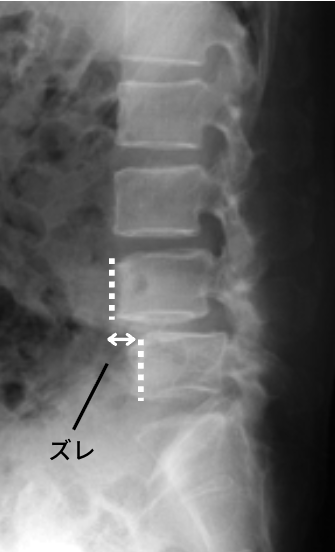

みなさんは「腰椎すべり症」という疾患を聞いたことはあるでしょうか?60~70代で特に多くなる腰のけがです。これは加齢によって腰のクッションがすり減ってしまったり、筋力が低下して起こるものなのですが、分離症を放っておくと10代からすべり症が完成してしまいます。

こちらは高齢者のすべり症の画像

(日本整形外科学会HPより引用)

上下の腰の骨同士が、まるですべってしまったかのようにズレているのがわかるかと思います。

このような“ずれ”が生じると、痛みを伴ったり、神経が圧迫されて下半身が痺れてしまったりと日常生活に大きな支障が生まれてしまいます。

分離症が起こっている場所は骨同士が支え合うことができないため、負担がかかり続けると雪崩のように骨のずれが発生してしまいます。

イラストのすべりはかなり大袈裟ですが、このように滑らないよう周りの筋肉が過度に働き腰痛を引き起こしたり、靭帯や神経を傷つけてしまいます。